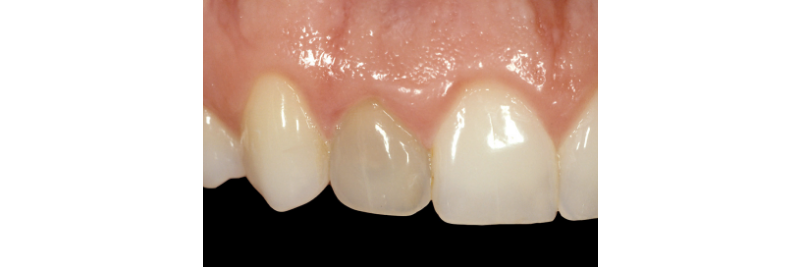

One of the most challenging clinical situations encountered in practice is restoring a “dark tooth” in the esthetic zone (Figs. 1A, 1B).

One treatment option that is often overlooked is internal non-vital tooth bleaching. This can be an excellent treatment option if the tooth has had RCT or needs RCT (Figs. 2A, 2B).